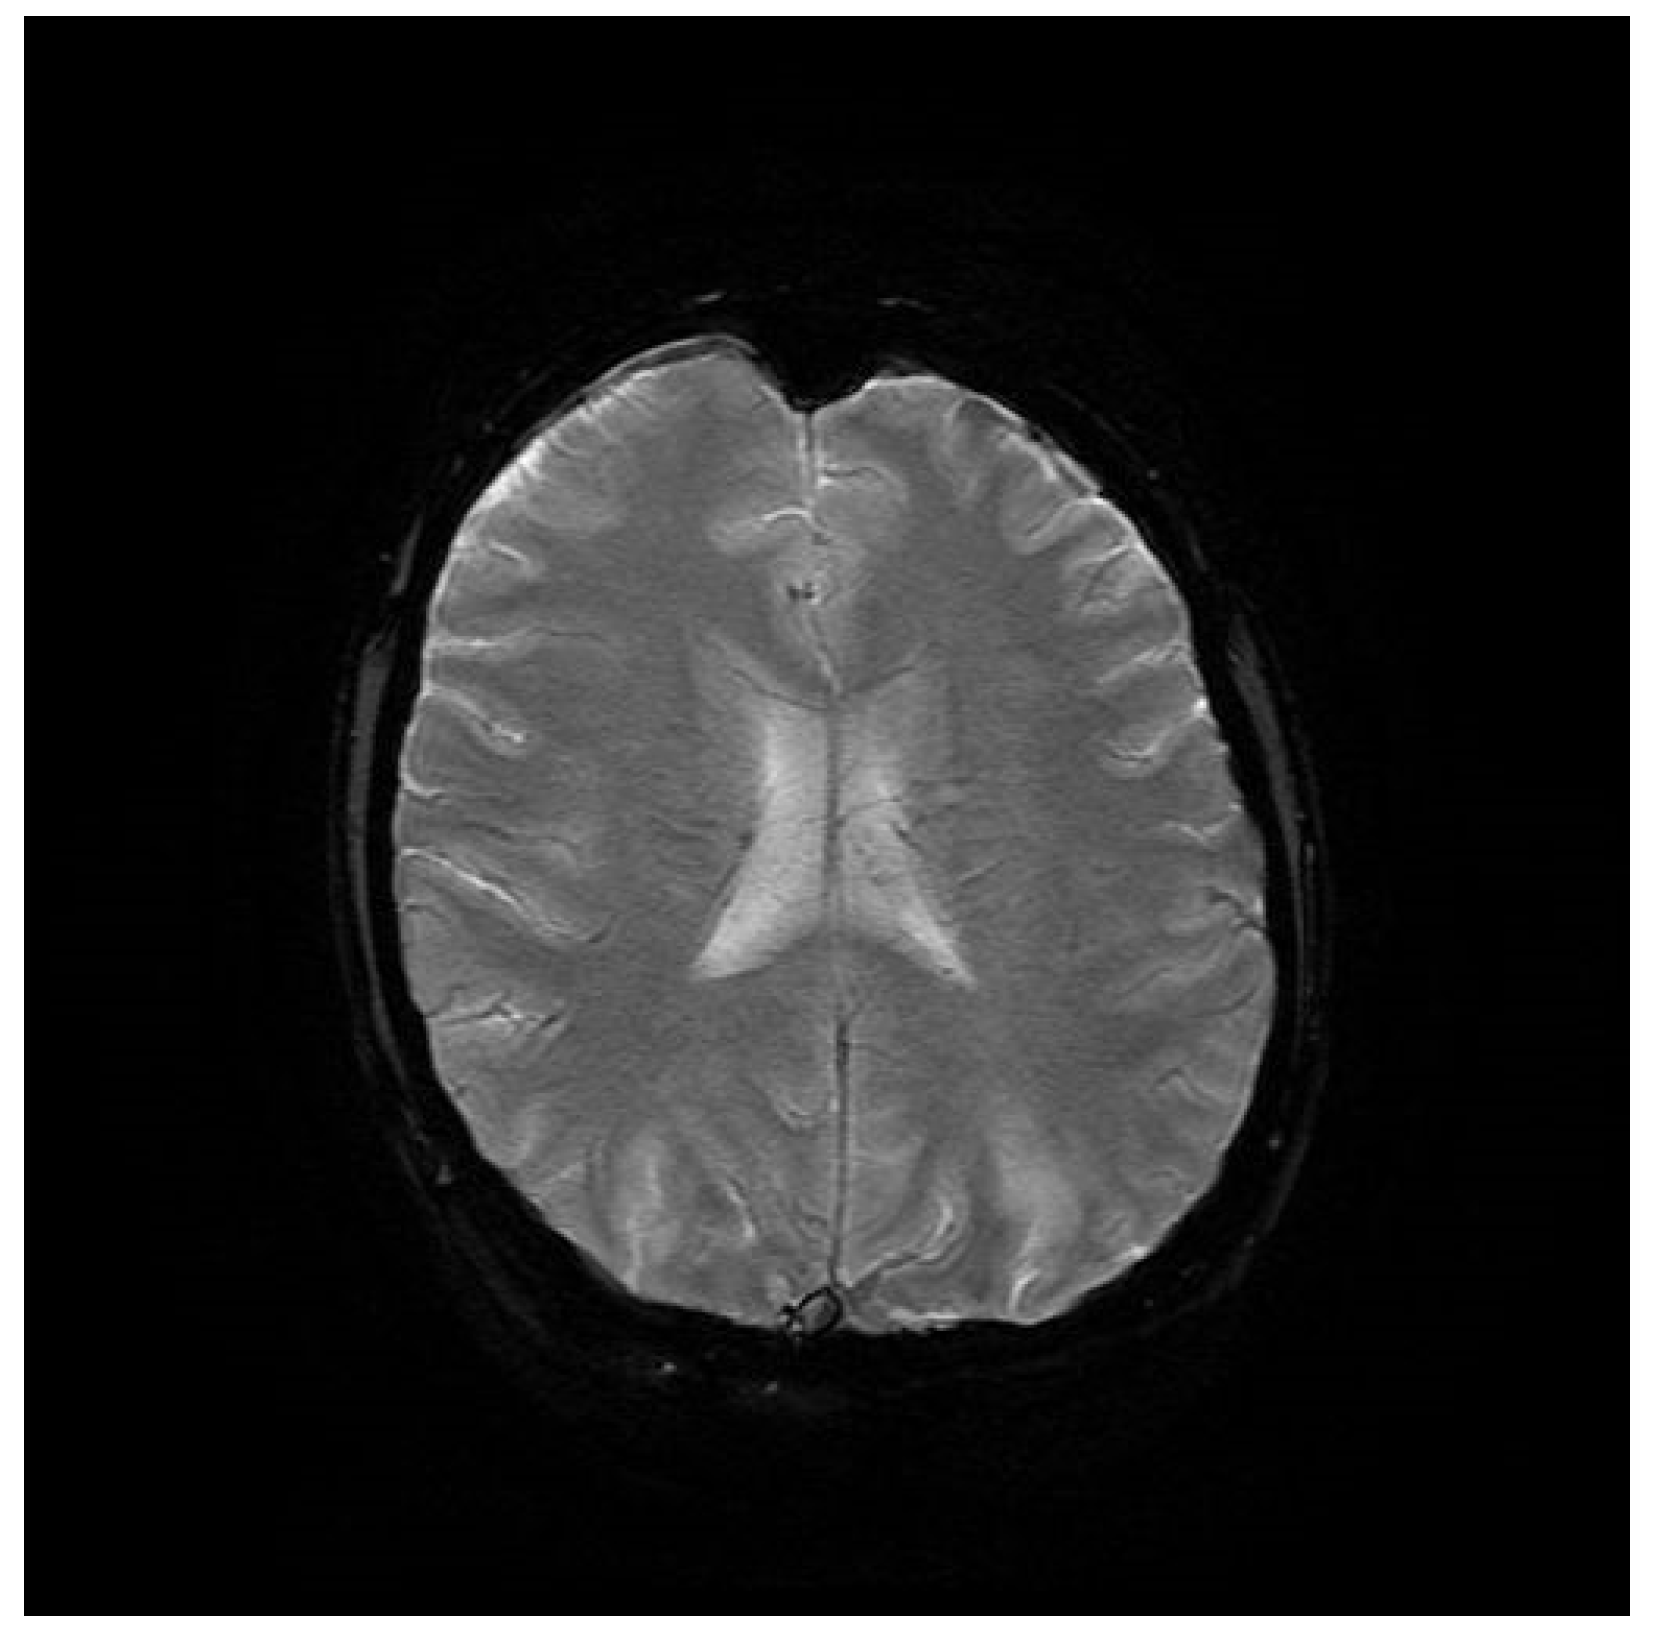

Computed tomography (CT) angiography of the head and CT with contrast were performed and excluded aneurysm, arteriovenous malformation (AVM), dural sinus thrombosis, and tumor. Due to the lack of deviations in the previous tests, an MRI of the head with contrast was performed, in which small areas and hyperintense bands in the T2-weighted image (T2-WI) and Fluid Attenuated Inversion Recovery (FLAIR) were visualized on both sides in the parieto-occipital areas without either diffusion restrictions or contrast enhancement, a typical manifestation of PRES [4], as shown in Figure 1, Figure 2, Figure 3 and Figure 4.

Figure 4. T2-WI MRI sequence of the brain in horizontal plane.